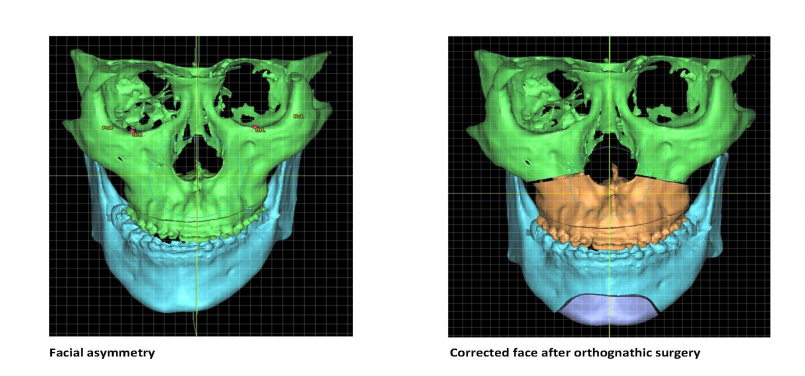

Facial asymmetry can be a result of the difference in jaws’ growth rate or caused by trauma. Patients with facial asymmetry will see a difference in the length of the left and right side of the jaws, which result in a deviated face as well as a shifted bite. The asymmetric face not only affects the facial appearance of the individual, but also hinders the eating or speech function and lowers the patient’s self-esteem.

Jaw correction surgery, or orthognathic surgery, is the surgical treatment for patients with dentofacial deformities including facial asymmetry. In the surgery, the deformed jaws are surgically corrected in a planned and normalized position so as to improve the patient’s masticatory and speech function, as well as symmetry and facial profile. It is a routine procedure performed by OMFS surgeons and will usually take three to six weeks to recover.

Since the result suggests TMD could be caused by facial asymmetry, the research team further investigated the effect of orthognathic surgery to correct facial asymmetry and the prevalence of TMD. It was found that the prevalence of TMD in patients with facial asymmetry who underwent jaw correction surgery has reduced by 58.3% at 6 months after the surgery. The finding indicates that surgical correction of facial asymmetry is effective in improving or even curing TMD in these patients.